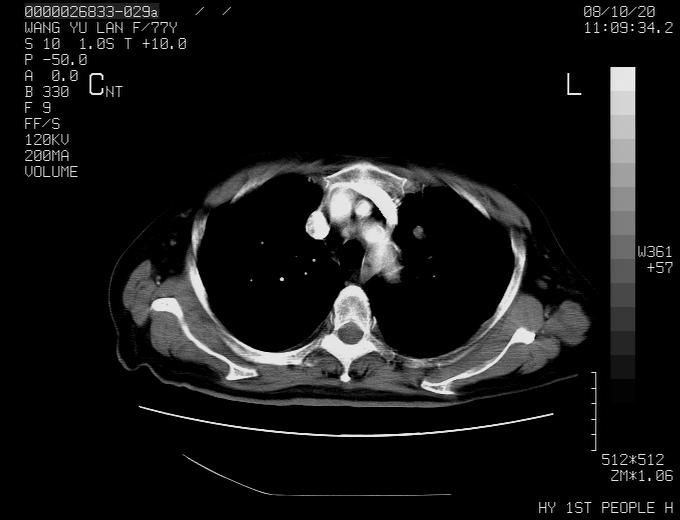

女性,77岁,胸部疼痛半月。左上肺团块影,本人考虑血管畸形,请分析

动脉期未见大血管同步强化,首先考虑周围型肺癌

动脉期病灶近中线侧可见星芒状与大血管同等强化密度,支持考虑血管畸形伴血栓形成,动脉期不曲型,不除外周围型肺癌

1、考虑avm可能性大。2、纵隔有肿大淋巴结,左肺上叶有炎性病变,不排除肺癌并转移可能。